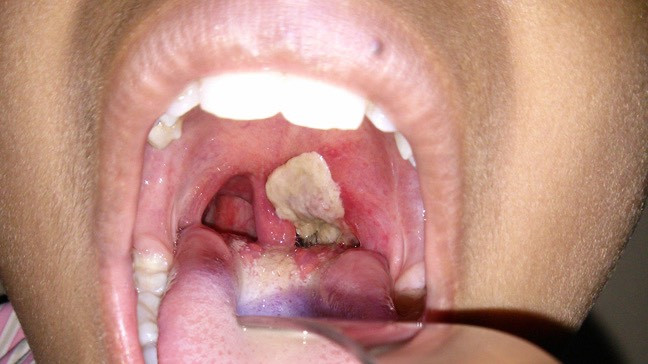

| Hình ảnh giả mạc trong bệnh bạch hầu - Ảnh BVCC |

Bệnh bạch hầu là bệnh nhiễm trùng - nhiễm độc, lây theo đường hô hấp và có khả năng gây dịch, do trực khuẩn Corynebacterium diphtheriae gây nên. Bệnh thường gặp ở trẻ em và ở đối tượng chưa có miễn dịch với bệnh bạch hầu do chưa được tiêm vắc-xin đầy đủ. Vi khuẩn khu trú ở đường hô hấp trên tạo giả mạc dai dính, khó bóc tách và sinh ra ngoại độc tố gây nhiễm độc toàn thân, nguy cơ tử vong do biến chứng tắc đường thở và viêm cơ tim.

Sau khi ủ bệnh từ 2-5 ngày, người bệnh thường có triệu chứng sốt nhẹ, đau họng, khó chịu, mệt mỏi, ăn kém, da xanh, chảy nước mũi, họng hơi đỏ. Đặc biệt khám họng thấy amidan có giả mạc trắng, lúc đầu nhỏ sau lan dần ra bao trùm họng và lưỡi gà, màu trắng, dai, bóc ra dễ chảy máu, hạch cổ sưng to làm cho cổ bạnh ra (bạch hầu họng).